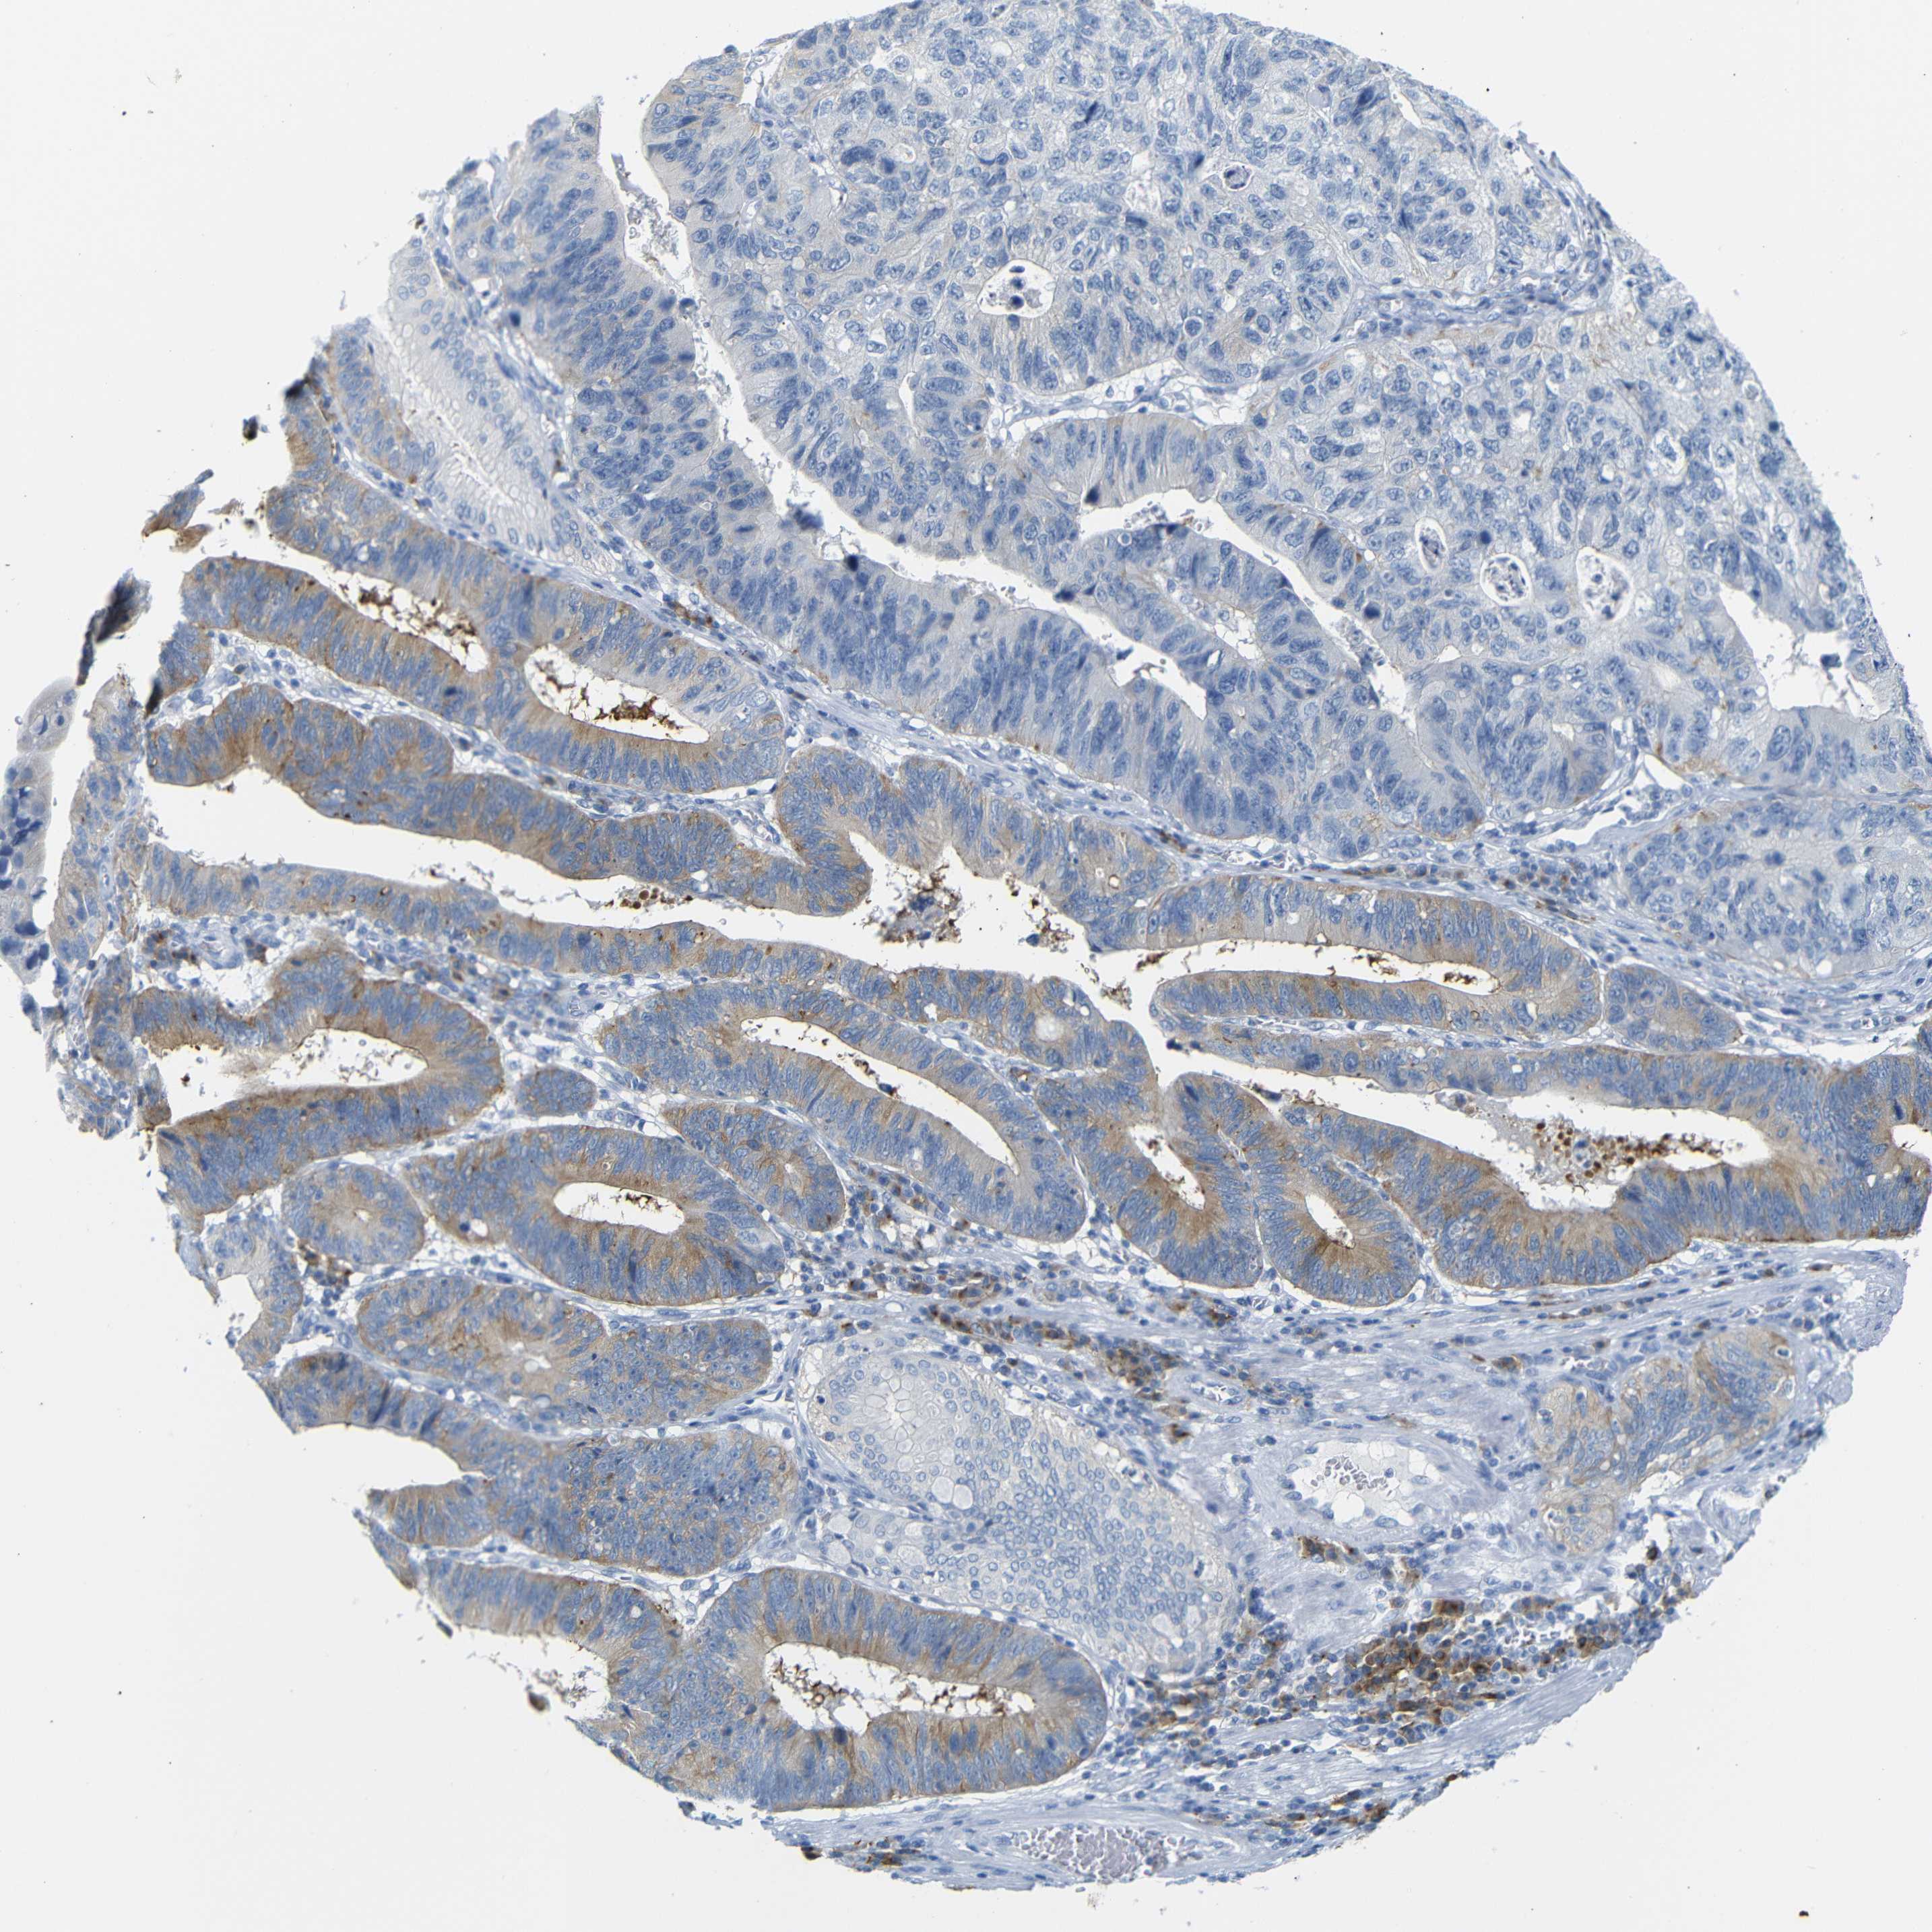

STOMACH CANCER - Protein expressioni

A mouse-over function shows sample information and annotation data. Click on an image to view it in a full screen mode. Samples can be filtered based on level of antibody staining by selecting one or several of the following categories: high, medium, low and not detected. The assay and annotation is described here.

Note that samples used for immunohistochemistry by the Human Protein Atlas do not correspond to samples in the TCGA dataset.

Antibody stainingi

Antibody staining in the annotated cell types in the current human tissue is reported as not detected, low, medium, or high, based on conventional immunohistochemistry profiling in selected tissues. This score is based on the combination of the staining intensity and fraction of stained cells.

Each image is clickable and will lead to virtual microscopy that enables deeper exploration of all samples and also displays staining intensity scores, fraction scores and subcellular localization as well as patient and tissue information for each sample.

Antibody HPA013323

Staining

High

Medium

Low

Not detected

Intensity

Strong

Moderate

Weak

Negative

Quantity

>75%

75%-25%

<25%

None

Location

Nuclear

Cytoplasmic/membranous

Cytoplasmic/membranous,nuclear

Adenocarcinoma, NOS

Adenocarcinoma, High grade